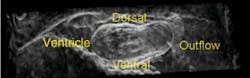

The recently developed FDML lasers have enabled unprecedented OCT imaging speeds.10 The high scan rate of these systems enables the acquisition of high-temporal-resolution 2-D image sets (195 frames per second) and 3-D datasets (10 volumes per second). The development of our FDML laser OCT system enabled, for the first time, an in vivo 4-D image of a preseptated embryonic avian heart without the aid of gating. This was also the first time the embryonic heart could be viewed in cross section during looping with extremely high temporal resolution, enabling the observation of morphological dynamics of the beating heart during systole (less than 50 ms in duration). Incorporating cardiac gating into the high-speed system will enable recording of 4-D image sets at 200 volumes per second, which will allow us to visualize and study systolic dynamics in three dimensions.

Images of a 2-day-old quail heart taken from a four-dimensional image set (with borders enhanced prior to volume rendering) demonstrate a visualization method that produces clearly interpretable results without resorting to time-intensive manual segmentation (see Fig. 3). This approach would be suitable for high-throughput and rapid preliminary phenotyping of internal and external embryonic structures, revealing the cardiac interaction with surrounding tissue.